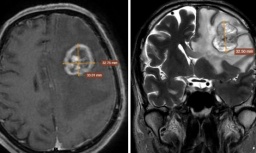

Sau khi cứu các em thoát khỏi lằn ranh sinh tử, quá trình chăm sóc các con cũng được nữ bác sĩ và nhân viên y tế tại đây theo sát từng ngày. Theo đó, các em bé can thiệp bào thai đều được Bệnh viện hẹn tái khám định kỳ để theo dõi. Các bé còn được thăm khám chuyên sâu, thậm chí chụp MRI để xem não bộ bé có bị ảnh hưởng sau khi can thiệp không. Bác sĩ sản còn kiêm luôn cả bác sĩ dinh dưỡng để tư vấn cho các bà mẹ về thực đơn dinh dưỡng, về sản phẩm sữa, thuốc tốt nhất cho các bé nhằm hỗ trợ thêm cho các bé phát triển khỏe mạnh.

Hiệu quả đạt được của chúng tôi ngang tầm thế giới, với 84,9% bé được cứu sống. Sản phụ sau can thiệp được theo dõi rất sát tới khi sinh con. Các em bé không chỉ được chào đời khỏe mạnh, mà còn được đánh giá về sức khỏe bằng thăm khám sau từng tháng chào đời. Chúng tôi còn chụp MRI để xem bé có tổn thương sơ sinh nào không.